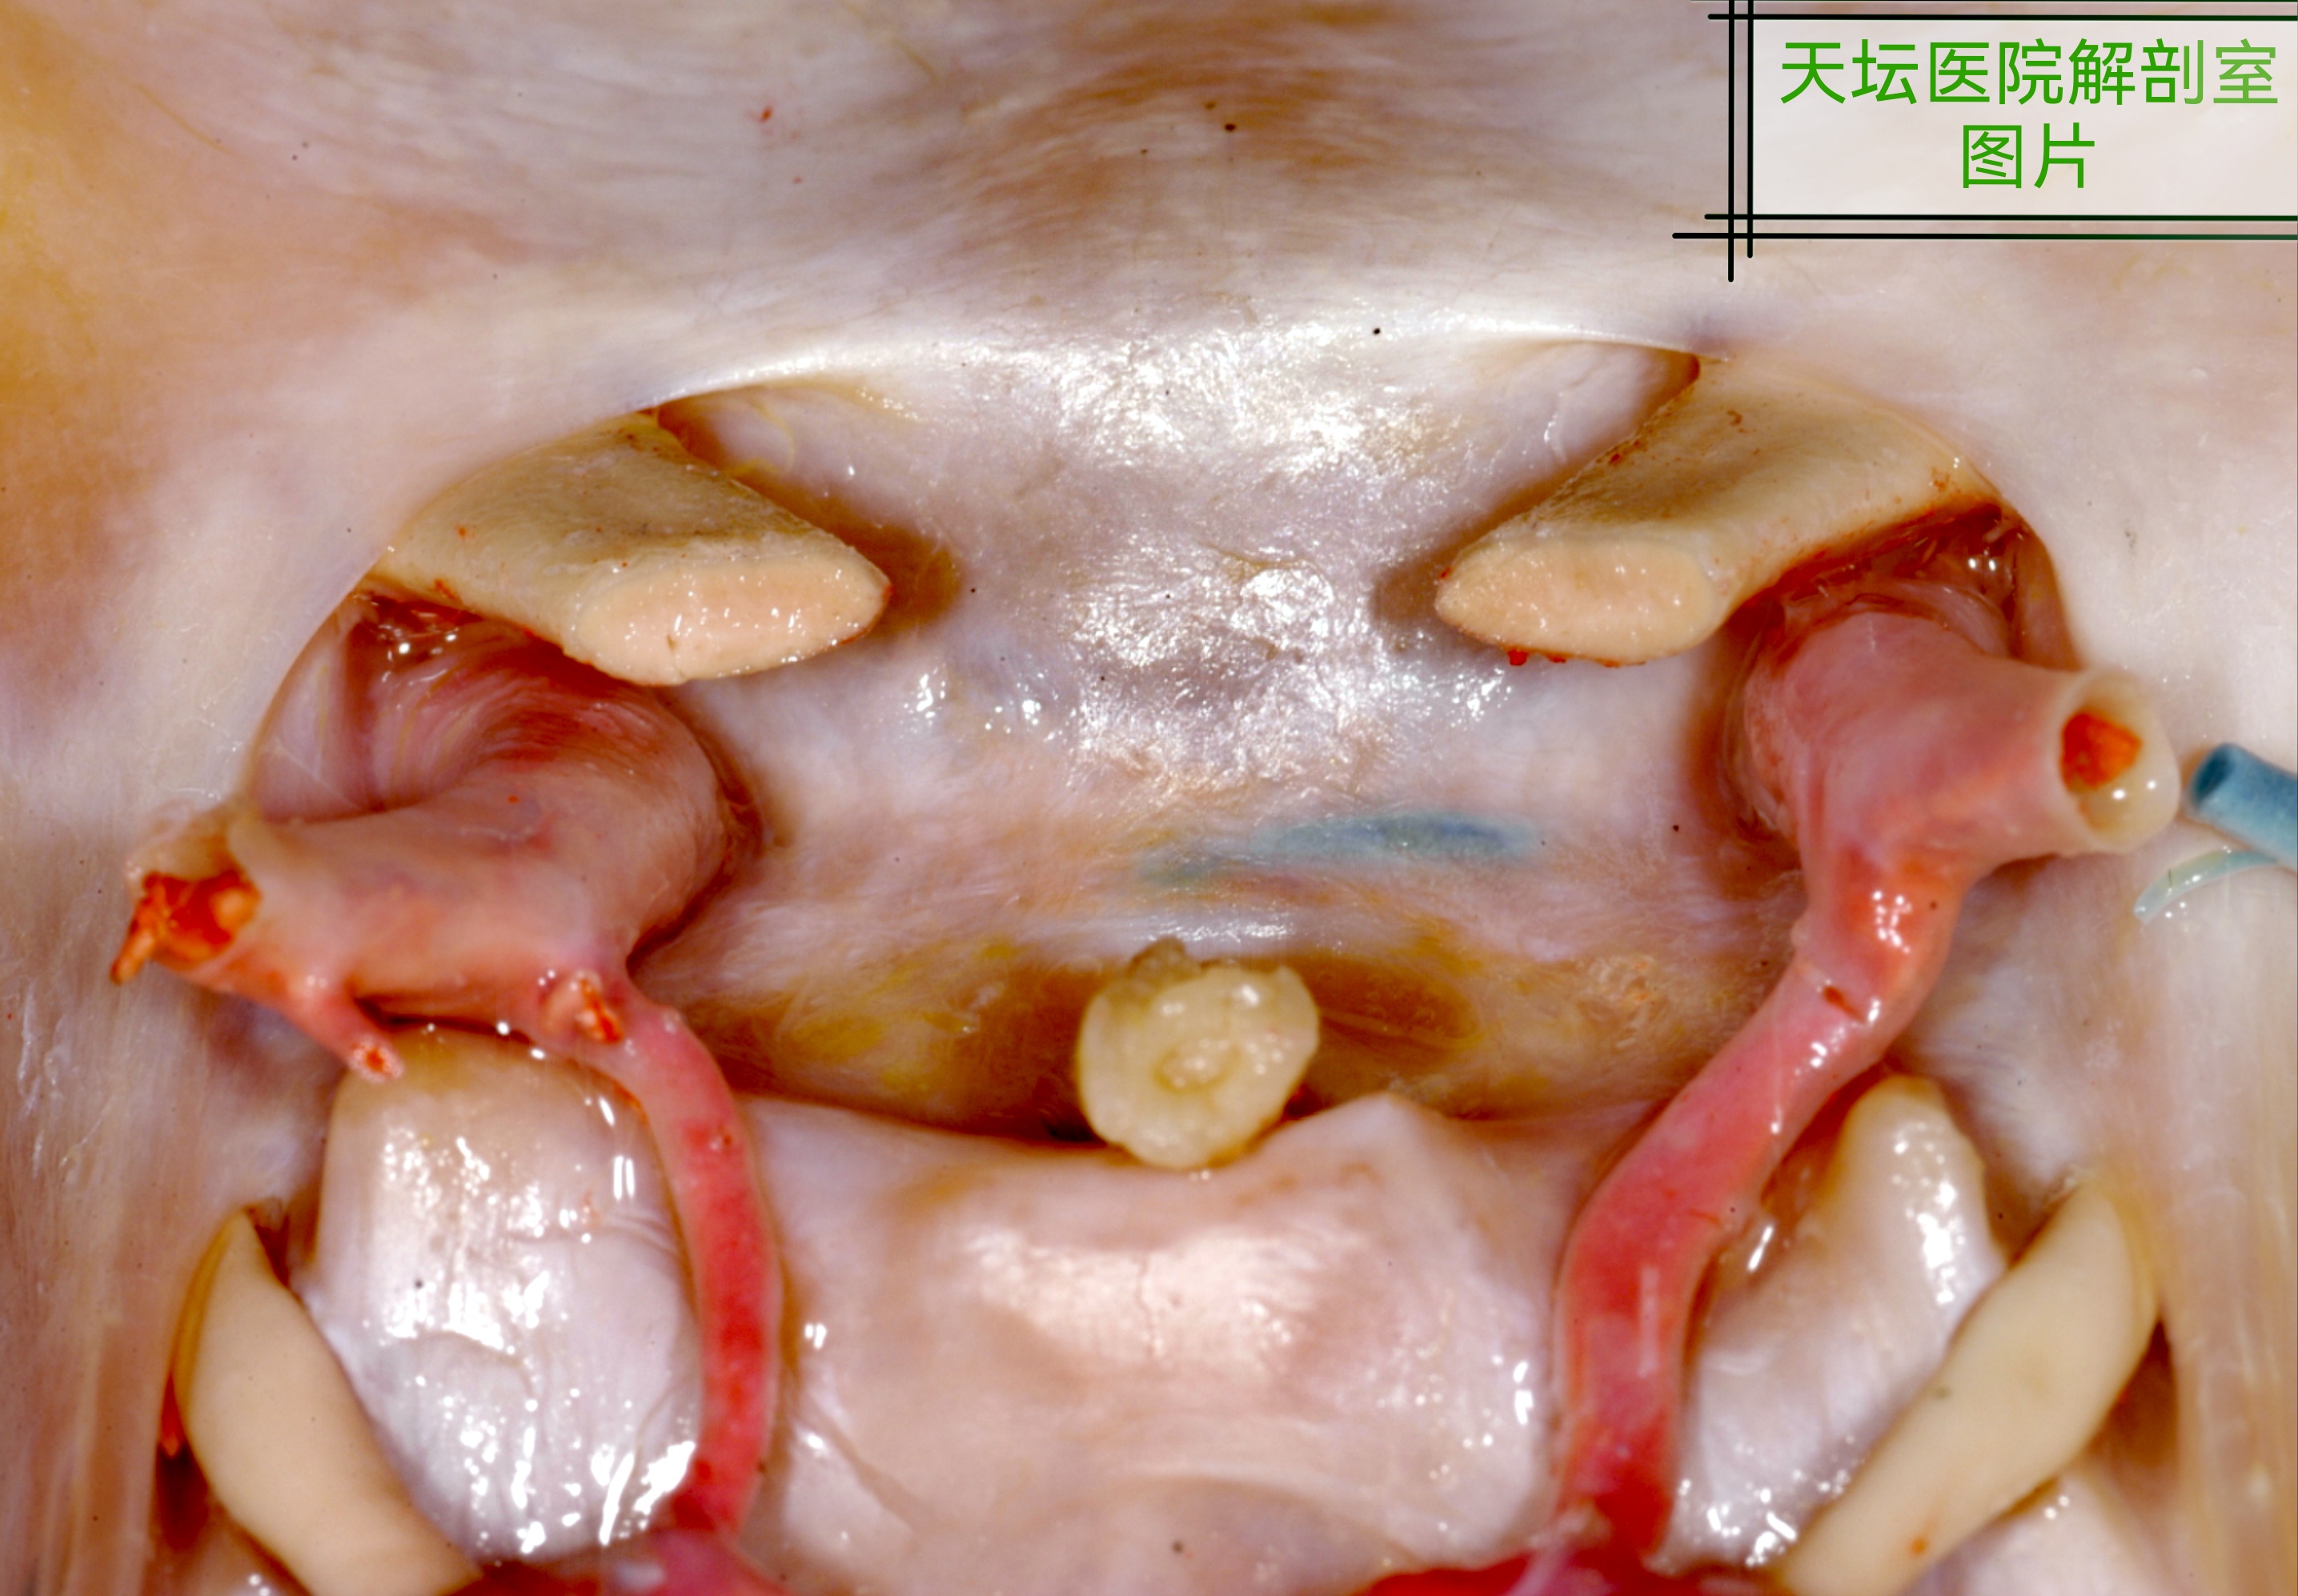

以下附几张天坛医院解剖室师兄们做的几张图片,方便

大家理解探查视神经管必要性。